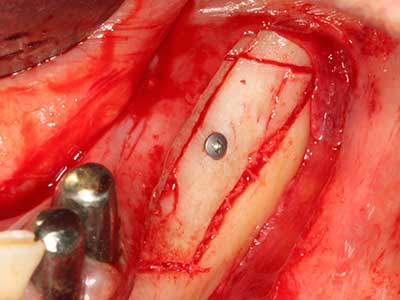

Indikation: Wurzelspitzenresektion

Sollen chirurgische Eingriffe mit unmittelbarer Knochenbeziehung an empfindlichen Strukturen wie Blutgefäßen oder Nerven erfolgen, so bergen rotierende Instrumente ein erhebliches Potential an iatrogener Schädigung. Gerade bei Nervdarstellungen nach iatrogener Schädigung, oder aber im Zuge einer Nervlateralisation für resektive und rekonstruktive Eingriffe oder Implantatinsertionen können piezoelektronische Geräte hilfreich sein Knochendeckel zu präparieren und nervnahe Hartgewebsanteile zu entfernen (Abb. 17-20). Ein leichter Kontakt des Nervstrangs zur Piezospitze bleibt dabei in der Regel folgenlos – allerdings kann eine unvorsichtige Vorgehensweise mit sägeartigen Bewegungen bzw. Ansätzen bei noch vorhandener knöcherner Unterlage durchaus temporäre oder aber auch permanente Nervschädigungen verursachen. Das Risiko einer solchen Schädigung wird jedoch als wesentliche geringer eingeschätzt als unter Anwendung von Säge- oder Fräsinstrumenten (Pereira, Gealh et al. 2014).